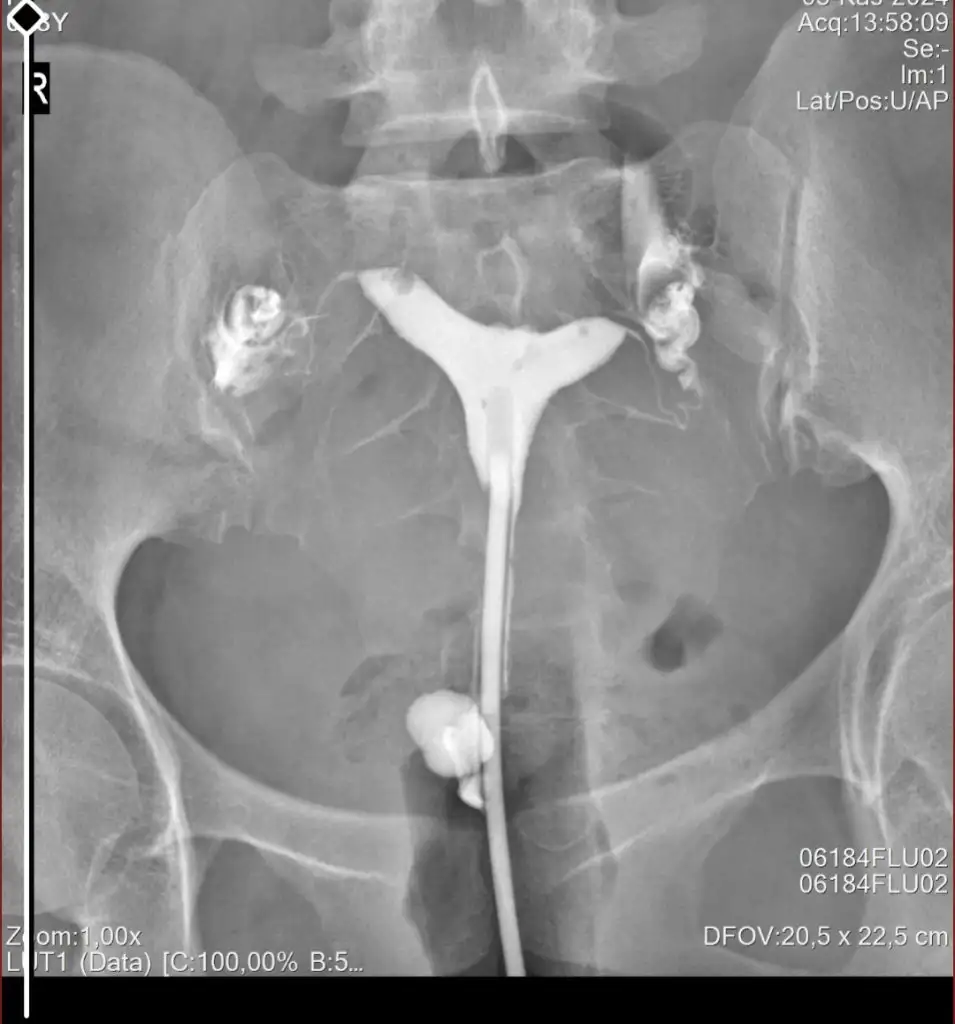

Ben de geçen hafta çektirdim HSG filmi. Raporum bugün oluştu ama anladığım kadarıyla sağ tüp açık sol tüp kapalı sanırım. Bana da yorumlama konusunda yardımcı olabilir misiniz? 4 senelik evliyim ve bebek sahibi olamadık, gebelik de hiç oluşmadı. Pcos'tan mustaribim. Tavsiyelerinizi alabilirim.

Canım rahim yapısı güzelmişT tubiikk Ekledim görüntüleri, teşekkür ederim.

Küçük yumuşak dokular gözükmüş bi kaç tane

Sağ tüpün açık sol tüpün kapalıymış ben öyle anladım görüntüde de biri kapalı gözüküyor zaten